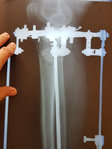

Рентген снимки через 1,5 месяца с момента снятия аппаратов